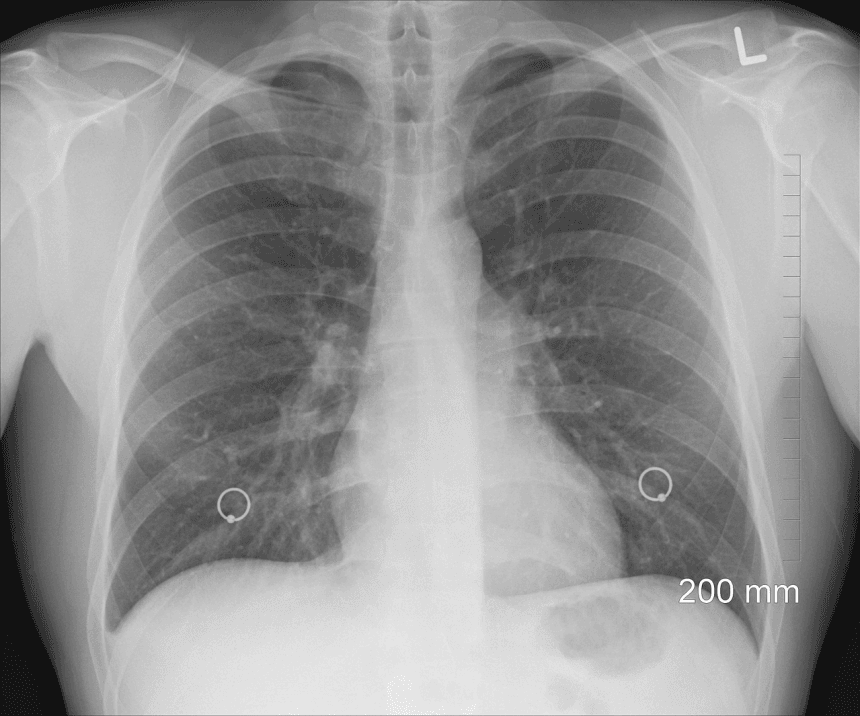

Исследователи из Университета Гисена нашли возможный новый подход к лечению смертельного заболевания легких. При идиопатическом легочном фиброзе происходит быстро прогрессирующее рубцевание легочной ткани. Пациенты страдают от раздражающего кашля и одышки, теряют выносливость и часто умирают от последствий заболевания.

Врачи из Гисена обнаружили, что легочная ткань пациентов с фиброзом содержит необычно большое количество белка под названием FUS. Этот белок ускоряет размножение клеток соединительной ткани, ответственных за образование рубцов.